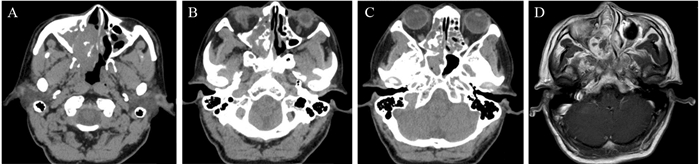

1 资料与方法 1.1 临床资料患者, 男, 59岁, 2016年5月1日以“右侧鼻腔新生物”收治于成都市第五人民医院。主诉:右侧鼻腔持续性鼻塞2年余, 加重伴脓涕、头昏痛2月。现病史:2年余前患者无明显诱因出现右侧鼻腔持续性鼻塞, 无脓涕及头昏痛等, 自服“感冒药”未见好转, 在当地医院就诊, 诊断为“右鼻息肉”, 建议手术治疗, 患者拒绝手术, 遂接受“丙酸氟替卡松鼻喷雾剂、通窍鼻炎颗粒”等保守治疗方案, 定期随访。2月余前患者自觉病情明显加重, 右侧鼻腔持续性鼻塞伴脓涕、嗅觉减退、无法通气, 同时伴间歇性头昏痛。不伴鼻出血及回吸涕带血, 无剧烈头痛伴恶心、呕吐, 无眼球运动受限及视力障碍或复视, 无面部异常隆起及感觉障碍等, 到我院就诊。一般查体:生命体征正常, 心肺腹(-); 专科查体:鼻外观稍饱满, 右侧鼻前庭见淡红色新生物, 包膜完整, 触诊实性、质地中等, 鼻腔及鼻咽部不能窥及, 左侧鼻腔未查见异常。纤维鼻咽喉镜检查:经左侧鼻腔查见鼻咽部正常; 右侧鼻腔见巨大淡红肉色新生物, 表面光滑, 包膜完整, 镜身无法进一步深入查探, 根蒂来源于中鼻甲内侧壁嗅区方向, 见图 1。鼻窦CT平扫:右侧鼻腔软组织密度影肿物, 边缘光滑, 境界清楚, 密度欠均匀, 邻近鼻腔外侧壁骨质压迫吸收变薄, 上颌窦、筛窦、蝶窦炎性积液, 鼻中隔不规则偏曲, 考虑右侧鼻腔良性肿物:血管瘤?鼻窦炎?见图 2。MRI检查:右侧鼻腔肿物, 充填鼻腔和鼻前庭, 最大径7.6 cm, 肿瘤根蒂部位于嗅区及鼻顶, T1WI显示以等信号为主, 肿块密度不均匀, T2WI显示高信号为主的混杂信号, 呈“三重信号征”, 颅内未见异常, 考虑倾向于右侧鼻腔恶性肿瘤, 见图 3。

| A-C: CT imagings showed that a lump with clear boundaries and smooth margins presented soft tissue density which resembled skeletal muscles, and a lump resulted in compressive bony absorption and moth-eaten changes happened inside wall of right maxillary sinus, and we also found some "peripheral calcifications" in the lump; D: horizontal T1WI of MRI showed that neoplasms mainly presented equisignal zones, located in nasal cavity and nasal vestibule. 图 2 鼻窦CT和MRI检查(横断面) Figure 2 CT and MRI findings of sinuses (transverse plane) |